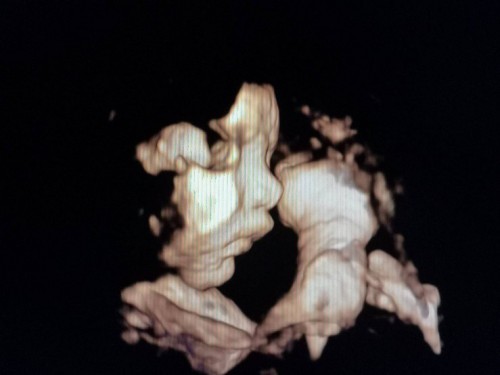

āđāļāđāļāļāļđ āļŦāļĨāļāļĨāļđāļ #āļāļāļāļđāđāļāļāļēāļ§āļāđāļāļĩāļĄāļāļļāļĨāļēāļŦāļāđāļāļĒāļāđāļ° ðĨ°ð§ļ